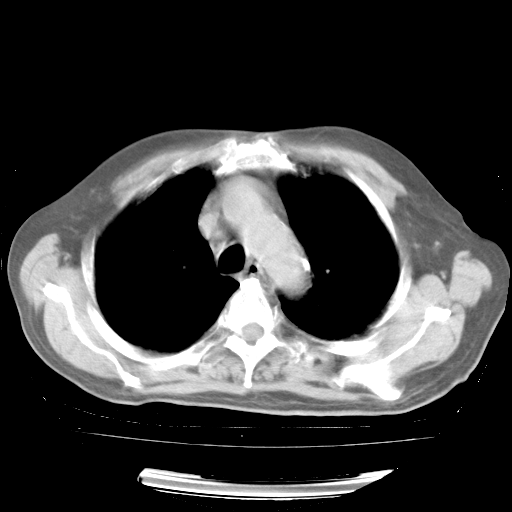

4月28日肺部CT——再次出现类似去年5月9日——磨玻璃样、间有“粟粒样”改变。